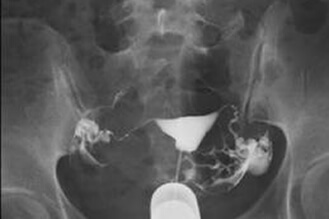

双侧输卵管水肿不通